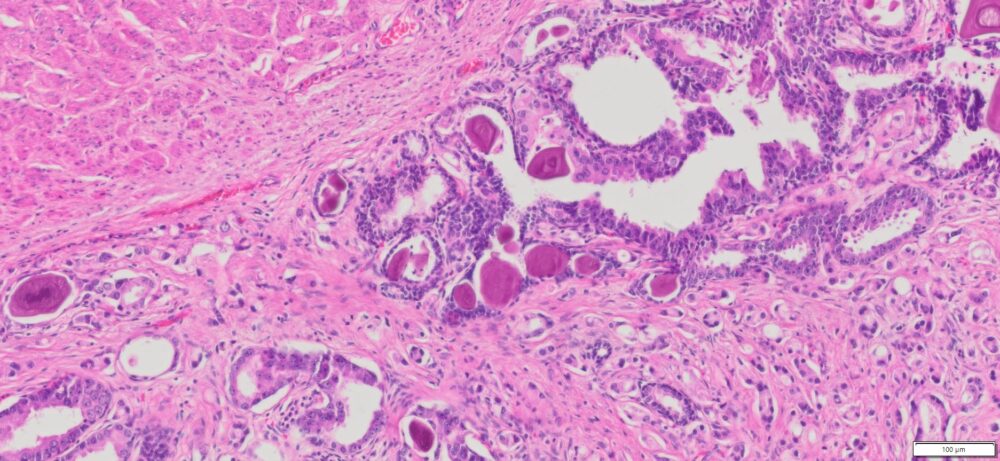

Description

| Tissue | Pathology Diagnosis | Gender/ Age (year) | %Tumor Area | Tumor Grade | TMN/Stage | IHC data |

| Prostate | Human Prostate Adenocarcinoma, Acinar type, Gleason score 9 (4+3) | Male/66 | 31% | II | pT3a, PNx Mx | NA |